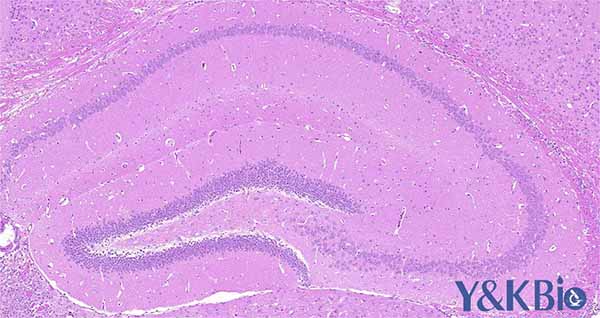

新疆石蜡切片实验中常见问题、原因及具体处理方案